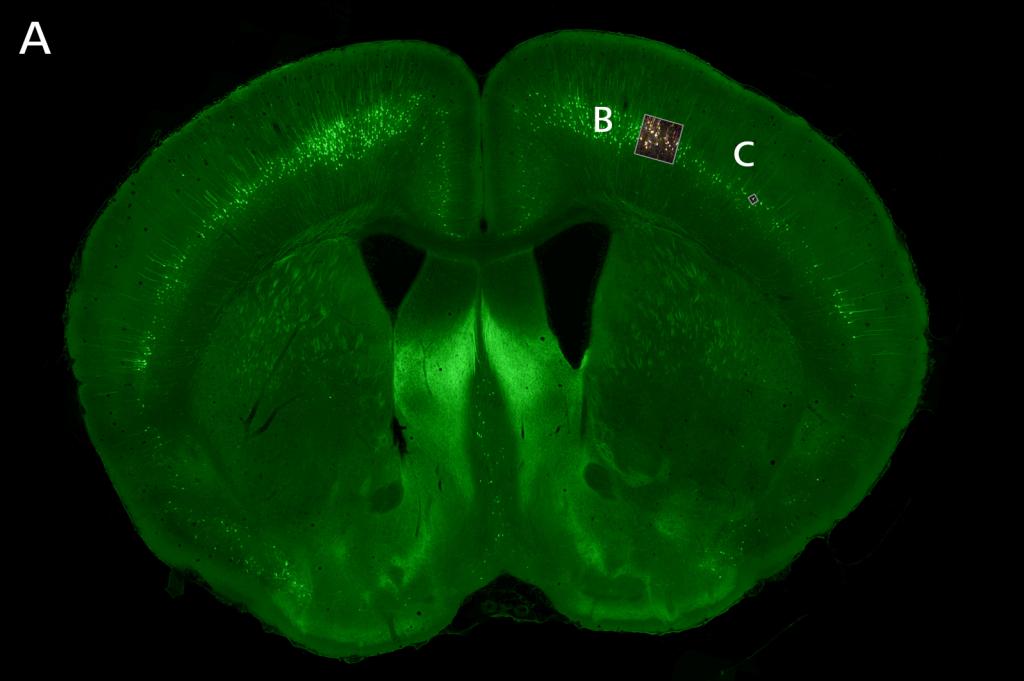

图片展示: